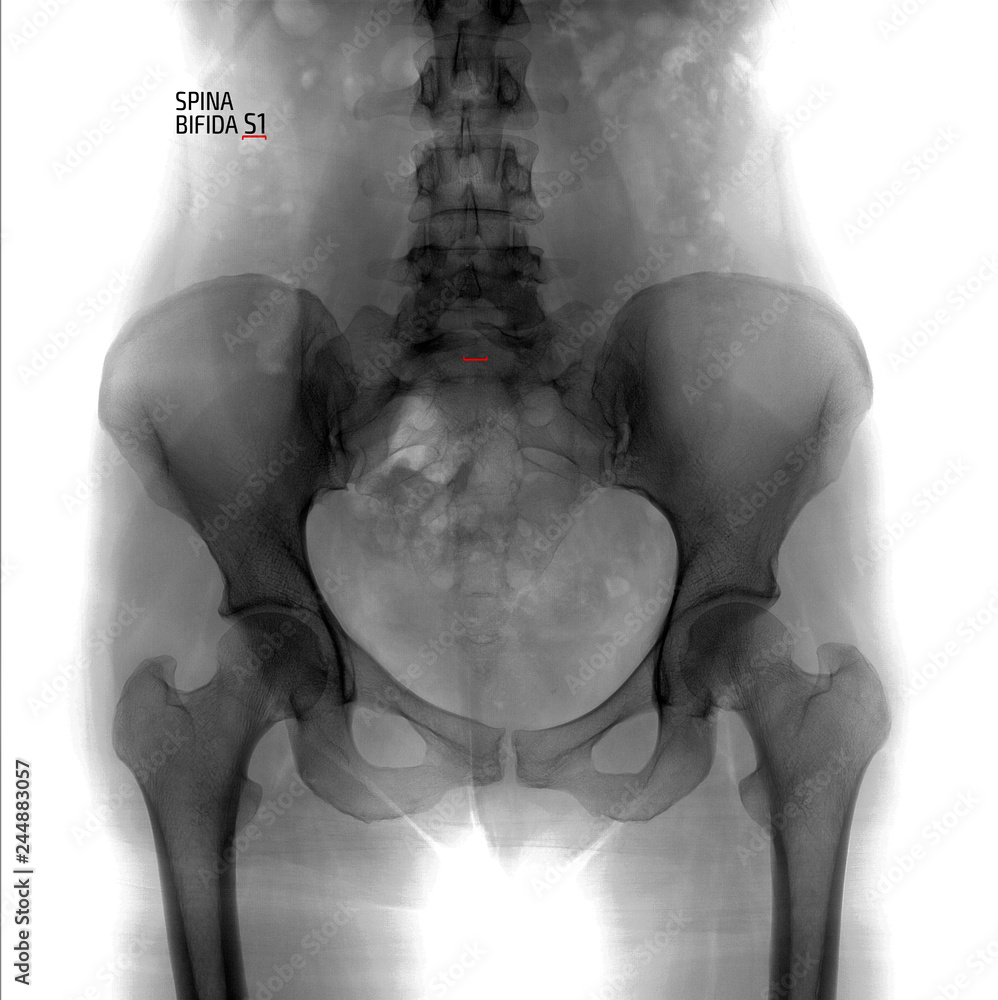

Рентген шейных позвонков при спина бифида

Раздел: Фотозарисовки